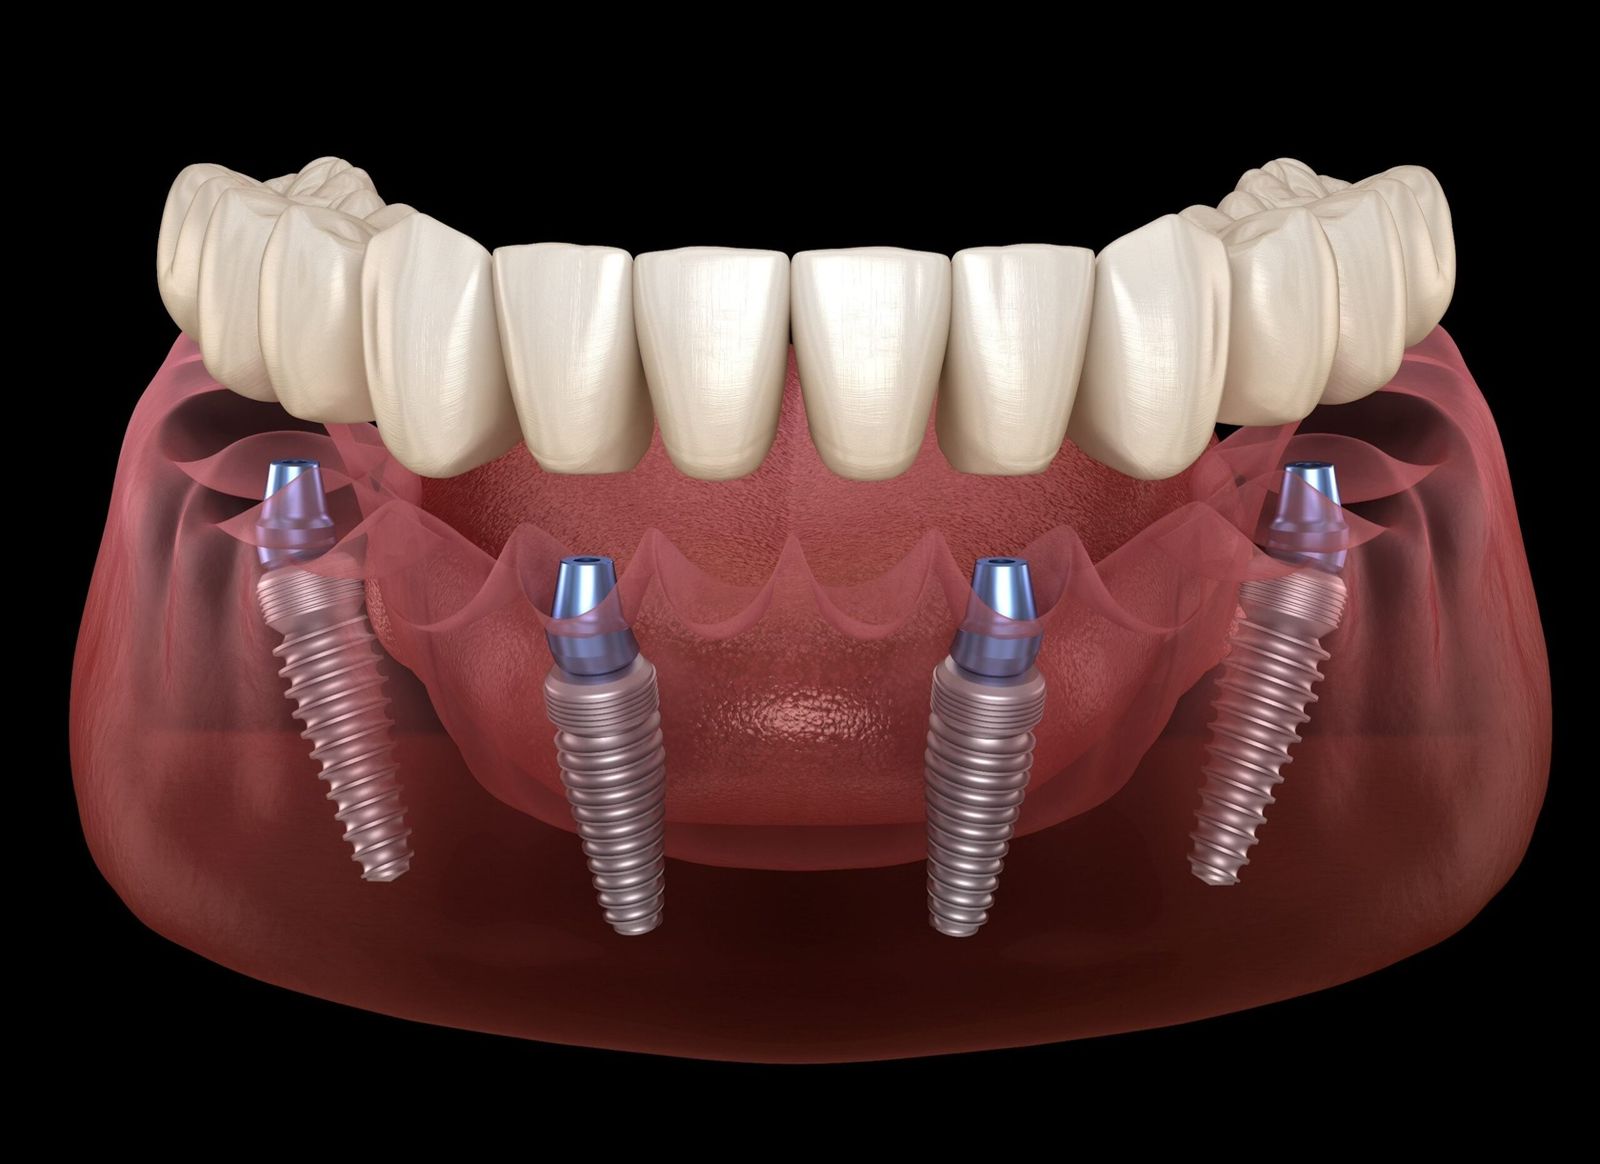

Implantes dentales: La solución ideal para recuperar tu sonrisa

Los implantes dentales son la opción más efectiva y duradera para reemplazar dientes perdidos. Gracias a esta avanzada técnica, es posible restaurar tanto la estética como la funcionalidad de tu dentadura sin comprometer ni desgastar las piezas dentales adyacentes al área desdentada.

Con implantes dentales, recuperas tu confianza, tu sonrisa y la capacidad de disfrutar plenamente de tus actividades diarias.